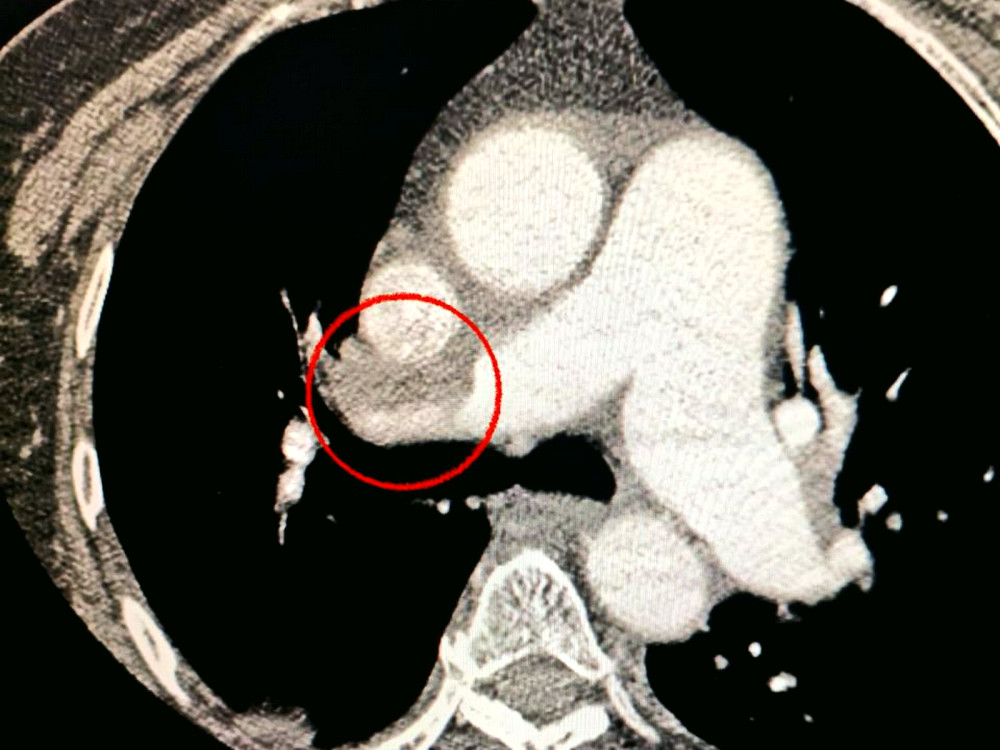

Пацієнтка, яка потрапила до лікарні з тяжким інсультом, під час комп'ютерної томографії отримала діагноз закриття середньої мозкової артерії.

Лікарі помітили також, що жінка має труднощі з диханням, тому провели додаткові дослідження легень, виявивши тромбоемболію.